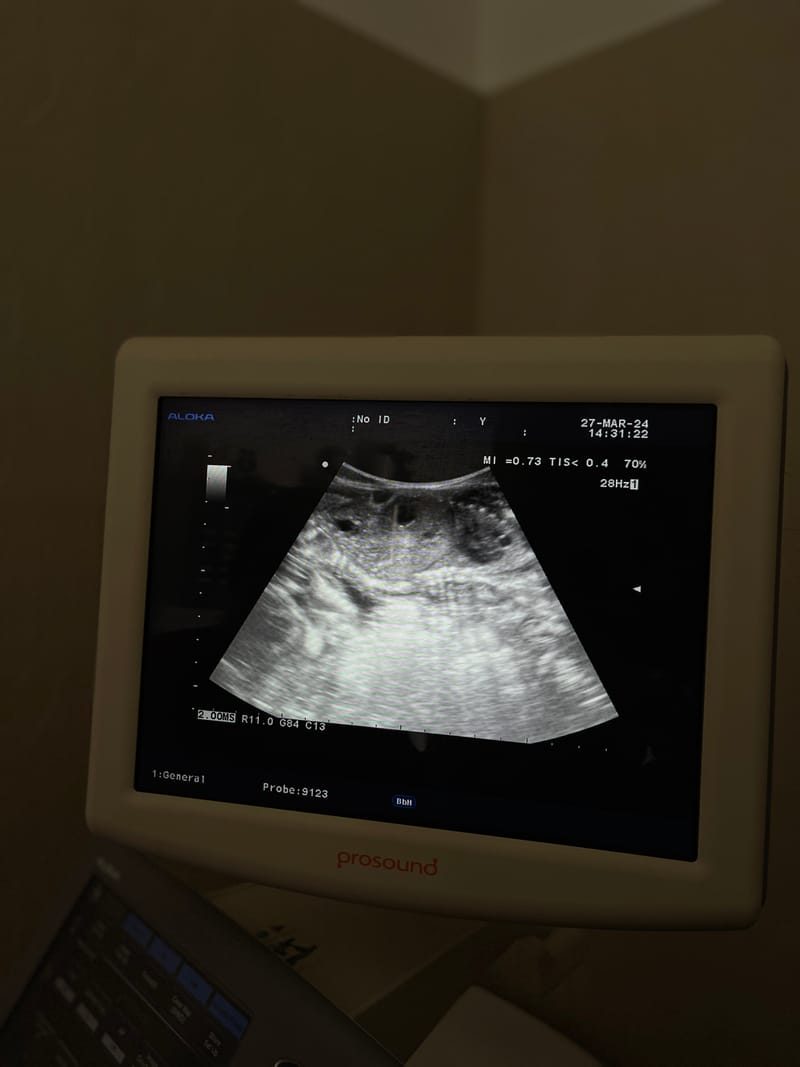

Examenul imagistic cel mai putin invaziv ce ne poate furniza informatii pretioase despre starea de sanatate a animalului dumneavoastra. Dispunem de 2 aparate de ecografie de inalta fideliatate cu ajutorul carora putem diagnostica cu acuratete multe afectiuni ale animalelor de companie.

Cel mai rapid si sigur mod de a confirma o gestatie la femele si de a monitoriza evolutia gestatiei este ecografia. Ecografia de gestatie este minim invaziva si "low stress", putand fi repetata de cate ori este nevoie pentru a asigura o gestatie si o perioada post-partum fara neplaceri.

In urgente una din anailzele cele mai importante poate fi ecografia abdominala de urgenta care ne permite sa intervenim corect pentru a salva viata pacientului nostru.